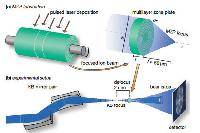

Мобильный рентгенаппарат + оцифровщик. Получение рентгеновского изображения на экране ноутбука. Вариант за 1,4 миллиона рублей под ключ.